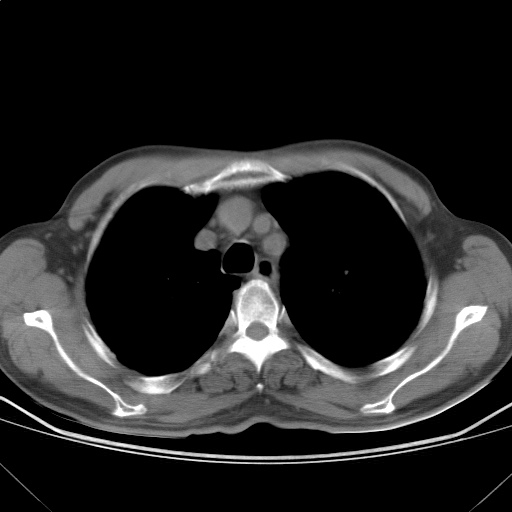

以下是引用随光逐影在2009-5-1 13:53:00的发言:[br]考虑为:1)两肺血行播散型肺结核;2)右肺下叶炎症感染。3)右侧胸膜增厚。